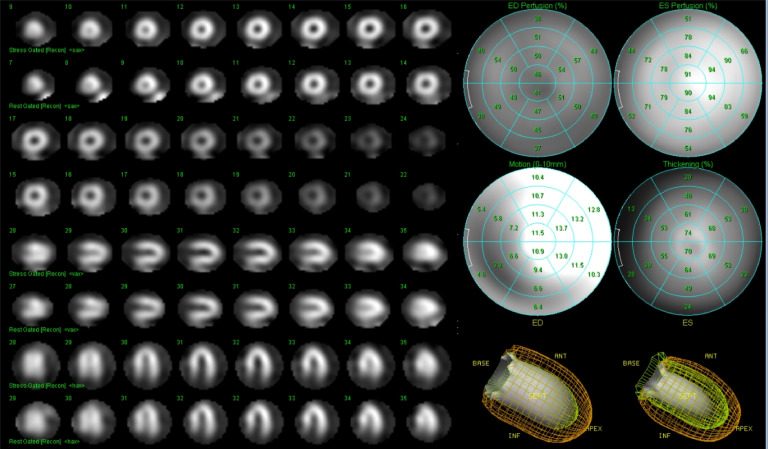

Fig. 4.

ECG-gated SPECT examination.

ECG-gated SPECT excluded akinetic and dyskinetic myocardial regions and confirmed valid ejection fraction.